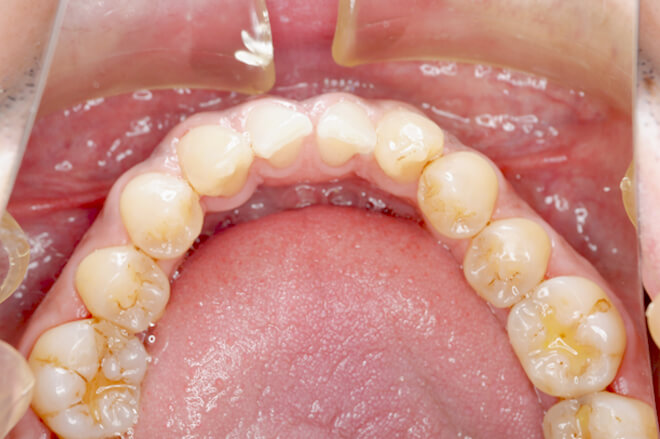

PMTC術後